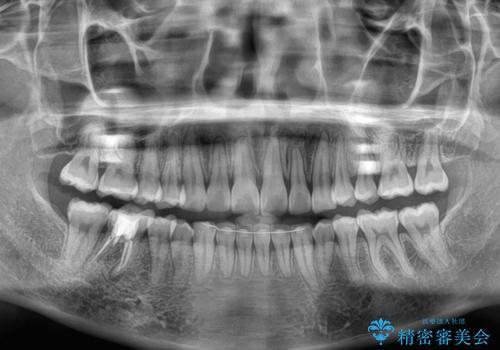

前歯のデコボコをインビザラインできれいに整える

前歯の捻れを改善するとともに、口元が少しでも引っ込むように治療計画を立て、仕上げることができました。

長時間の装着や、定期的な来院がままならず、想定よりも長期間の治療となってしまいました。